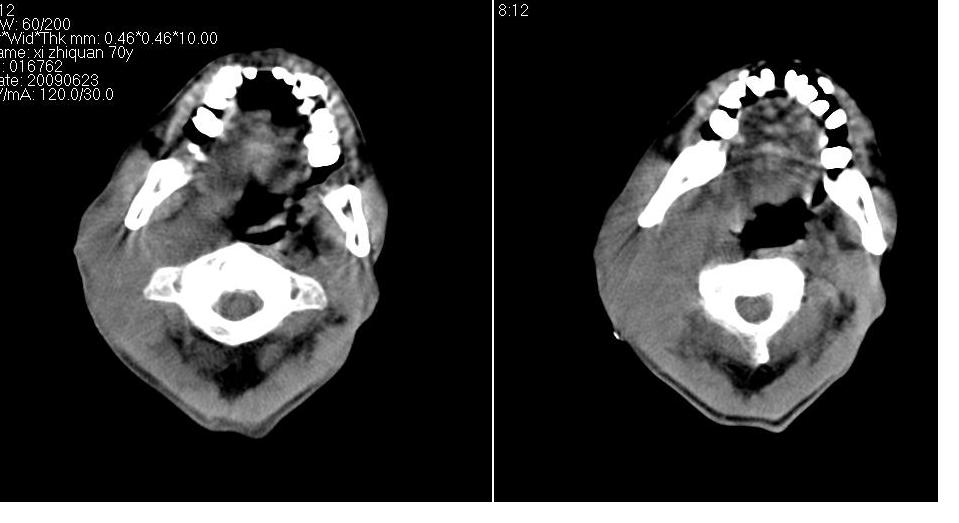

男 70岁,右侧颈部包块八个月余,下午及夜间疼痛加剧,包块质硬。化验穿刺镜下可见大量成堆裸核上皮细胞,可符合结核性淋巴结炎。

右侧颈部不规则软组织密度肿块影,密度均,边缘不清,颈筋膜间隙闭塞,向内致口喉咽受压变形,外达胸锁乳突肌深部,与之分界不清,周围骨质未见异常。